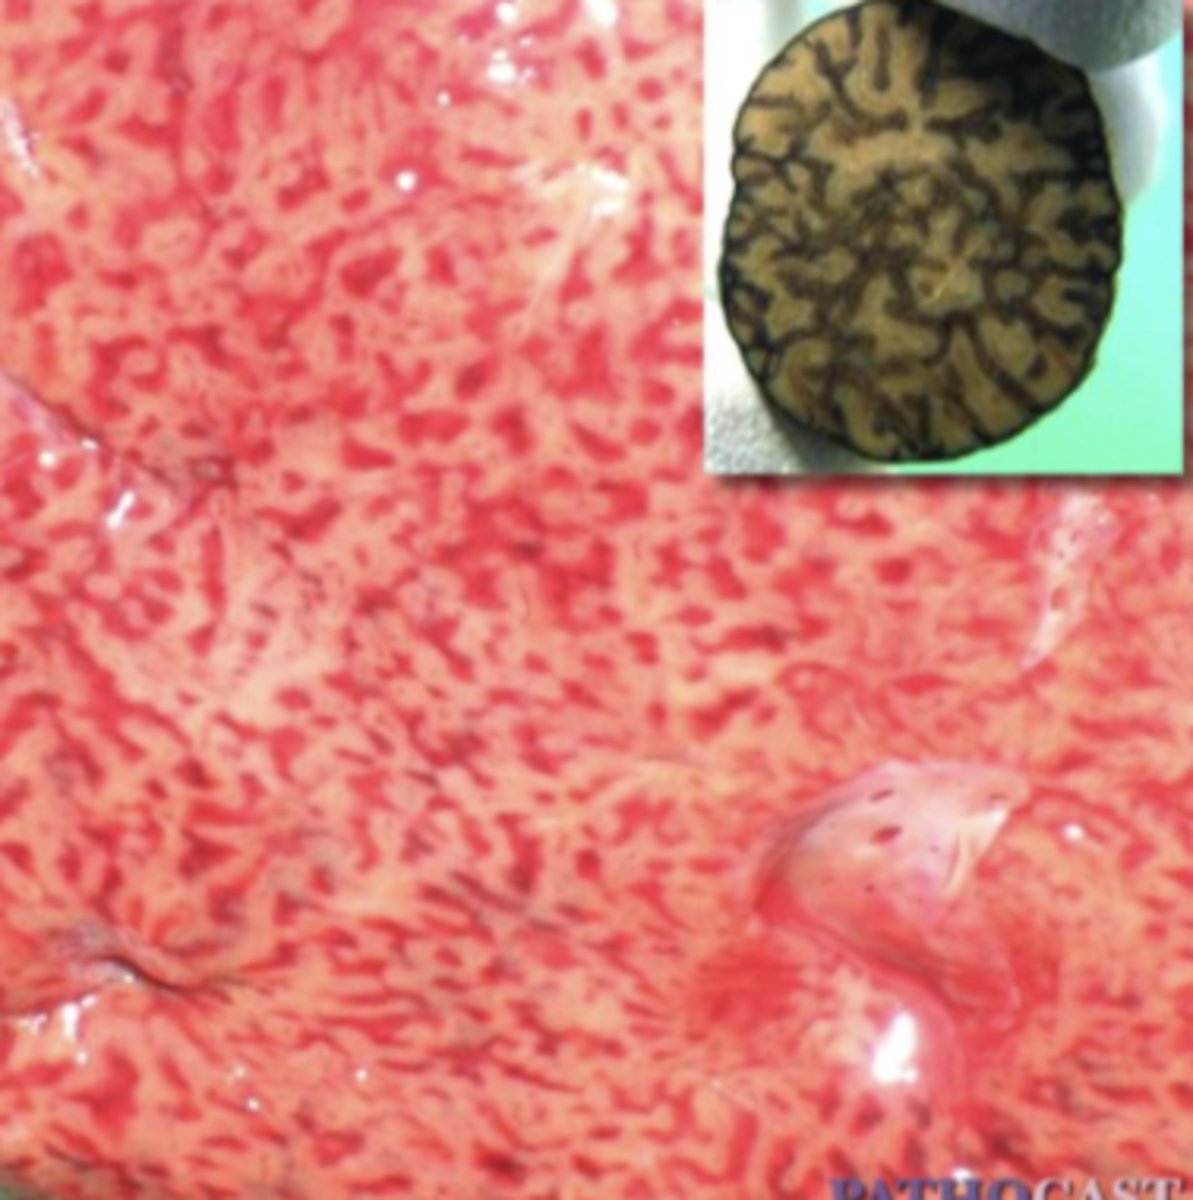

Parasite migration

-black lines indicate where parasites have migrated through

(hemorrhagic tracts)

- white spots/lines are scars from previous migrations

What has caused this gross appearance of this sheep liver?

Fascioloides magna migration

-black lines

-hepatocytes have filled with fat (white spots) due to hypoxia

-fibrous connective tissue from damage

What has caused this gross appearance of this liver?